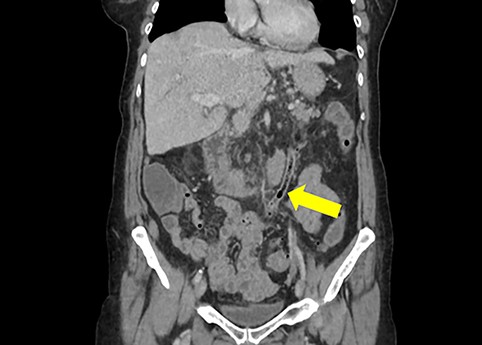

A non-contrast-enhanced computed tomography (CT) scan of the abdomen and pelvis was performed. This demonstrated acute sigmoid diverticulitis with air tracking along the course of the inferior mesenteric vein (Figs 1 and 2). Additionally, a large portal vein thrombus was seen with extension to the left intrahepatic portal vein (Fig. 3) and evidence of portal venousgas.

Coronal section of non-contrast CT scan demonstrating the colovenous fistula between the inferior mesenteric vein and sigmoid colon (yellow arrow); air is seen tracking within the lumen of the inferior mesentericvein.